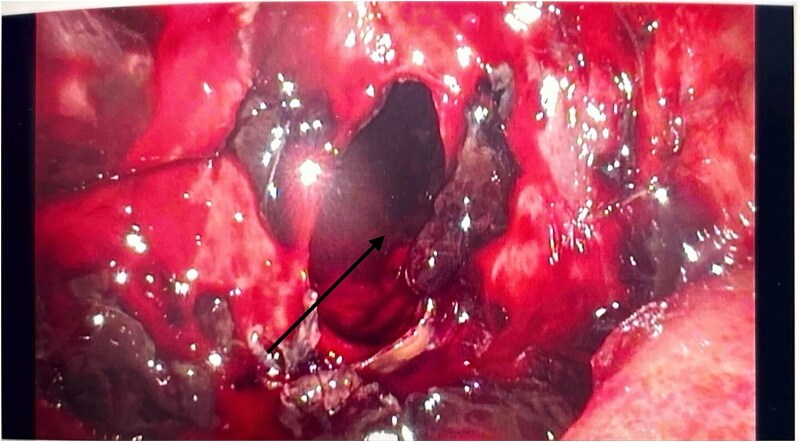

Acute necrotising pancreatitis can lead to severe vascular complications, including venous thrombosis, pseudoaneurysm, and haemorrhage. Acute haemorrhagic pancreatitis, though rare, is life-threatening. Contrast-enhanced computed tomography (CT) scan is the preferred diagnostic tool, with image-guided embolisation as the primary treatment for bleeding vessels. Surgery may be necessary when radiological methods fail. A 39-year-old male with recurrent abdominal pain, distension, and weight loss was initially misdiagnosed with intra-abdominal malignancy based on CT findings of omental deposits. Elevated amylase levels and haemorrhagic ascetic fluid prompted further investigations. A rapid haemoglobin drop and clinical deterioration led to diagnostic laparoscopy, confirming acute haemorrhagic pancreatitis. This case highlights the diagnostic challenges of this condition, which may present subtly and evade standard imaging, resulting in delayed treatment. Clinicians should suspect haemorrhagic pancreatitis in patients with acute abdominal pain, elevated amylase or lipase, and ascites. Early recognition and intervention are crucial for better outcomes.